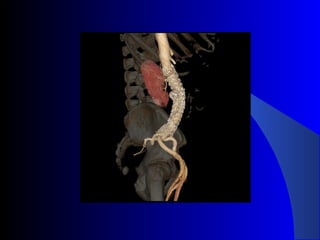

The document discusses the clinical application of the Endurant stent graft system in treating aorto-bisiliac aneurysms, detailing procedures performed on two male patients aged 72 and 73. Each patient had a history of dyslipidemia and carotid atherosclerosis, with procedures involving the bilateral bell bottom technique and the use of coils and fibrin glue. It includes pre-surgery imaging, intrasurgery angiography, and follow-up control scans to monitor outcomes.